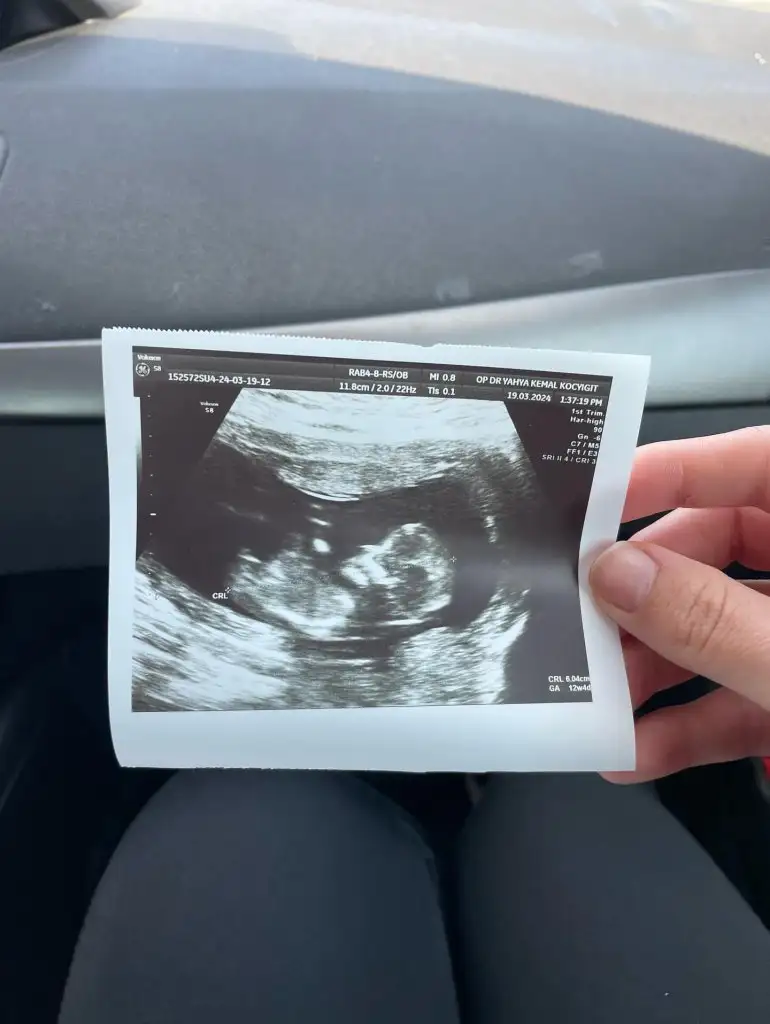

Kız gibi canımBurda 10 haftalığız

Tamamen hissiyatıma göre söylüyorum kız gibi geldi bana12 haftalık bizede bakar mısınız